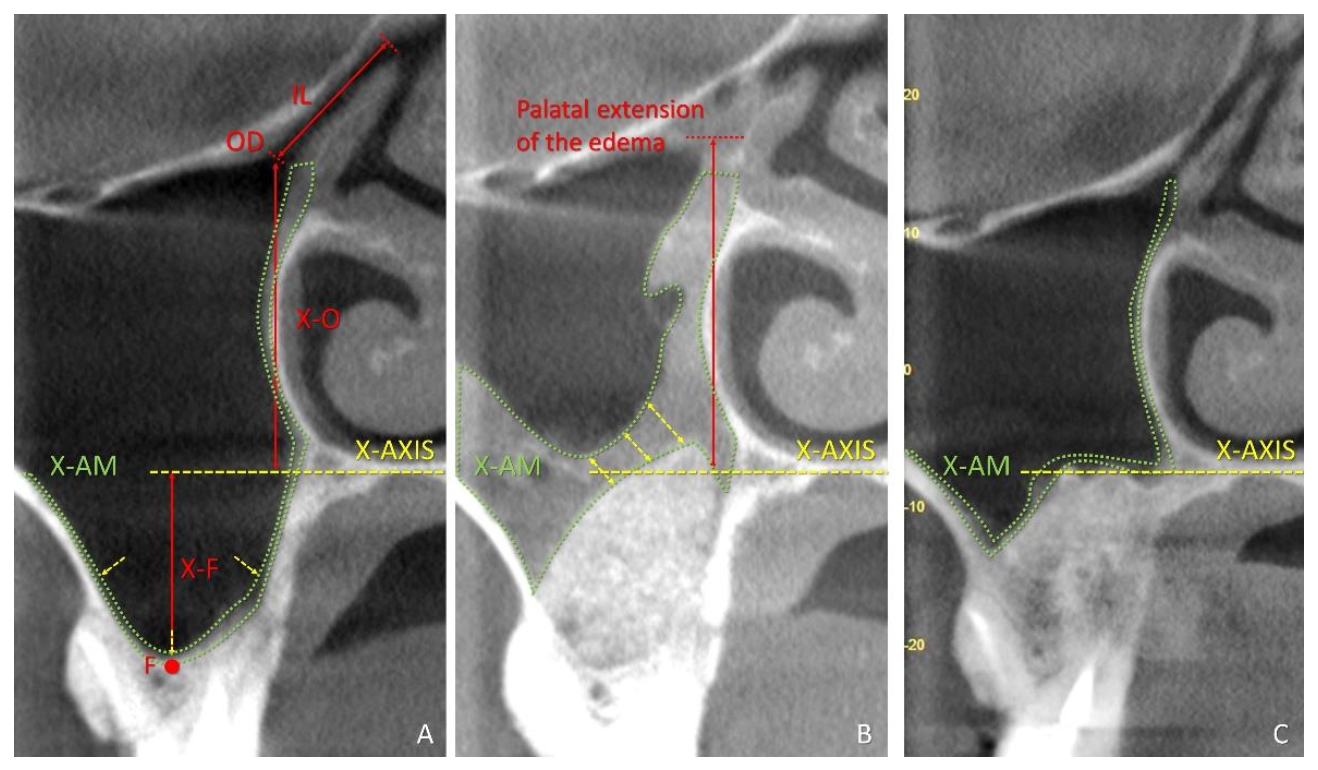

| MSO to X-Axis | MSO to Sinus Floor | Infundibulum Length | MSO Diameter | Number of Obstructions | Mucosa Thickness | Mucosa Area | Distance between Ostium and Edema | ||

|---|---|---|---|---|---|---|---|---|---|

| SEPTA Mean values ± SD Minimum; Maximum | T0 | 24.2 ± 3.4 18.5; 31.1 | 33.2 ± 3.9 25.2; 38.4 | 8.5 ± 1.3 6.3; 10.8 | 1.7 ± 0.4 b 1.3; 2.7 | 0 | 1.1 ± 0.7 b 0.3; 2.3 | 13.2 ± 8.3 b 5.6; 27.1 | - |

| T1w | - | - | 1.0 ± 0.6 b,c 0.0; 2.2 | 3 (20%) | 6.7 ± 7.8 b,c 0.5; 31.2 | 168.7 ± 161.0 b.c 7.9; 576.4 | 11.8 ± 10.7 c −1.4; 29.5 | ||

| T9m | - | - | 1.6 ± 0.4 c 1.3; 2.2 | 0 | 0.9 ± 0.6 a,c 0.5; 2.4 | 14.3 ± 7.3 a,c 10.0; 27.8 | 24.6 ± 6.0 c 9.8; 31.9 | ||

| CONTROL Mean values ± SD Minimum; Maximum | T0 | 24.9 ± 4.1 13.7; 30.0 | 32.6 ± 4.6 26.3; 41 | 9.2 ± 2.1 7.0; 13.6 | 2.1 ± 0.8 b 1.2; 4.6 | 0 | 1.0 ± 0.7 b 0.5; 2.4 | 14.7 ± 15.7 b 5.4; 66.3 | - |

| T1w | - | - | 1.0 ± 0.8 b,c 0.0; 2.5 | 5 (33.3%) | 8.2 ± 7.0 b,c 0.9; 24.1 | 199.9 ± 135.7 b,c 11.3; 449.5 | 7.5 ± 8.8 c 1.5; 24.7 | ||

| T9m | - | - | 1.6 ± 0.7 c 0.6; 2.9 | 0 | 2.3 ± 2.8 a,c 0.6; 11.4 | 44.0 ± 69.1 a,c 8.7; 283.0 | 21.5 ± 8.0 c 11.7; 34.7 |